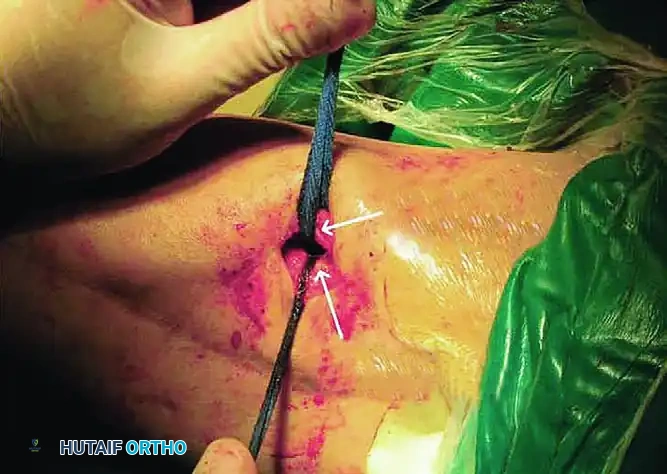

STAGE 4: Transection of the Vastus Intermedius

- If flexion remains inadequate after the first three stages, proceed to Stage 4.

- Transect the previously mobilized vastus intermedius at a level near its musculotendinous junction. In knees with moderate arthrofibrosis, these first four stages often allow knee flexion of more than 120 degrees, at which point the procedure can be terminated.

STAGE 5: Quadriceps Tendon Lengthening

For severe arthrofibrosis, the fifth stage is mandatory to gain more than 90 degrees of flexion.

- Transect the rectus femoris at a more distal level than the vastus intermedius, adjacent to its patellar insertion.

- Deliver the free tendinous ends of the vastus intermedius and the rectus femoris through the surgical wound.

- Gently manipulate the knee in flexion repeatedly until maximal passive flexion is achieved.

- Overlap the proximal tendinous end of the vastus intermedius and the distal portion of the rectus femoris tendon.

- Suture the overlapped tendons using a No. 2 nonabsorbable braided suture (e.g., Ethibond) with the knee held strictly in 90 degrees of flexion.

Dynamic Tensioning Pearl: Test the passive range of motion after repairing the quadriceps tendon. The lengthened tendon must be under substantial tension but remain competent at 90 degrees of flexion.

- If the knee flexes easily beyond 90 degrees: Increase the overlapping of the tendons by advancing the vastus intermedius tendon more proximally. This reduces the risk of a severe postoperative extension lag.

- If flexion is restricted: Decrease the overlapping by fixing the vastus intermedius tendon more distally.